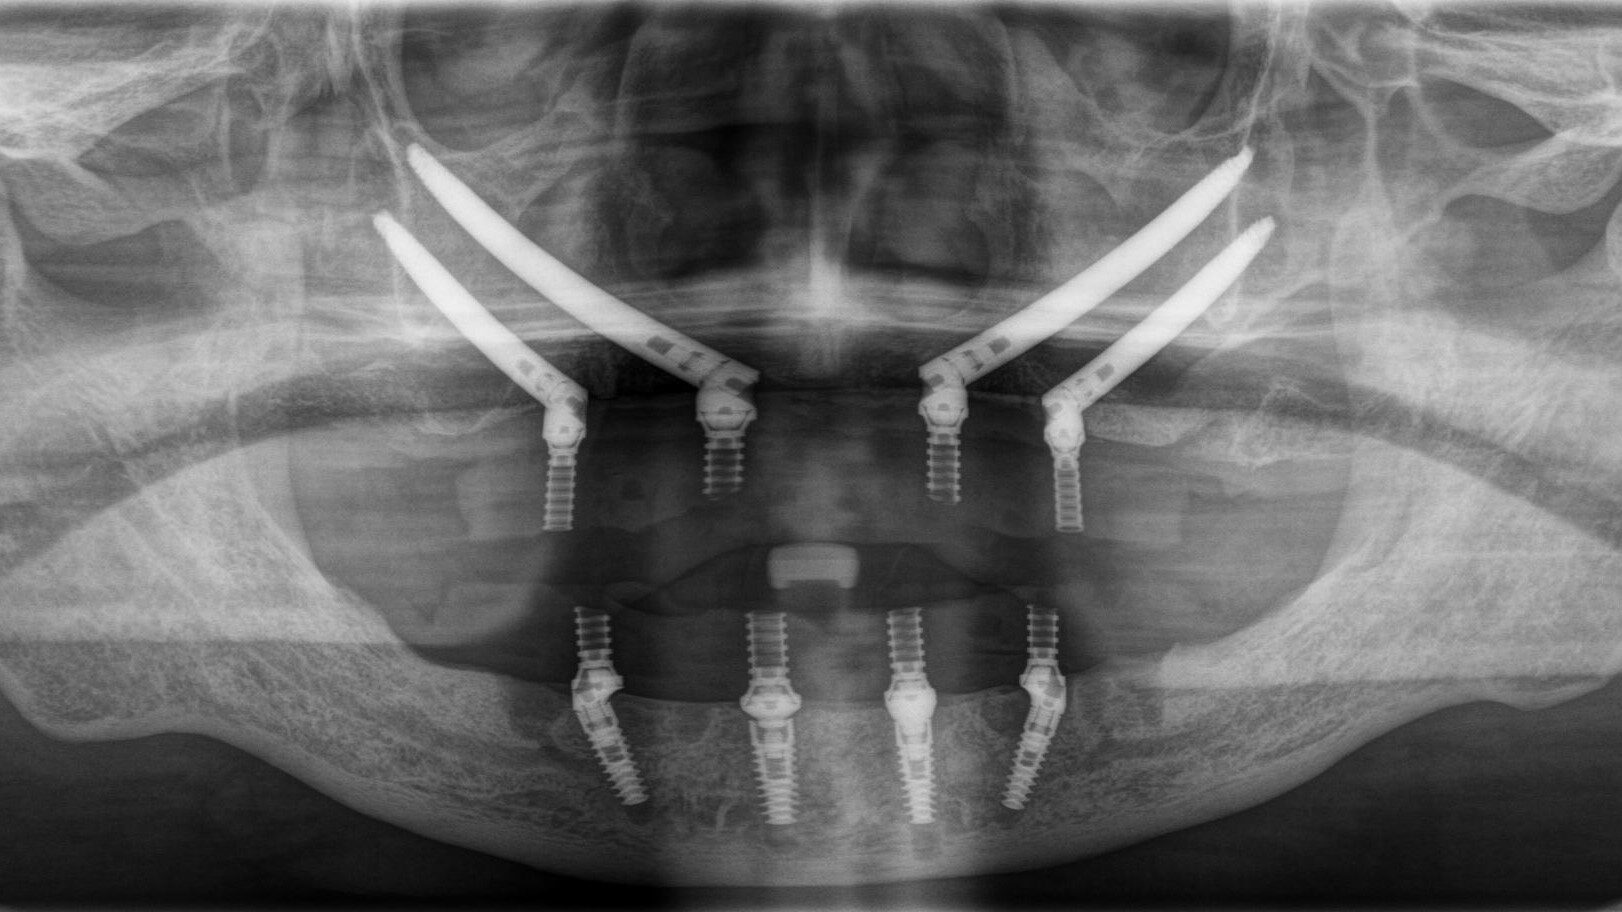

上下All-on-4

上顎:オールオン4ザイゴマ4本

下顎:オールオン4

Before

After

歯科医院にインプラントを相談しても「骨が全くない」「入れ歯しか無理」「オーバーデンチャー」と言われた患者さんのレントゲン画像です。

手術終了 術後ですが静脈鎮静麻酔なので意識が聡明になるのがとても早いです。小休憩後、術後のパノラマX線の撮影を行い、インプラントが適正な位置に施術できているかを確認します。その後、噛み合わせの調整などを行います。当日にお帰り頂き翌診療日に傷口の確認をさせていただきます。